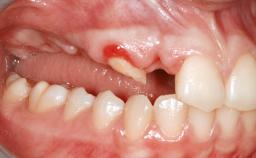

A 47-year-old Caucasian woman with a single-tooth edentulous space at the site of the left maxillary canine was referred for treatment. She had undergone traumatic extraction of this impacted canine several months before referral. Her chief complaint was the dissatisfying appearance of her smile. The patient desired a stable and esthetic rehabilitation of the site. Her dental history showed no evidence of periodontal disease or bruxism. She had no systemic diseases, was not taking any medications, and did not smoke. The extraoral examination revealed a high lip line and an inadequate soft-tissue volume at the defective canine site. Large black triangles were visible between the canine and its adjacent teeth.